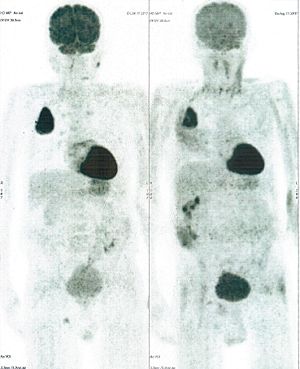

CASE NO: 2 (HEPATOCELLULAR CARCINOMA)

A 40+ man with hepatocellular carcinoma, an incurable cancer. After 2 treatment, the activity of the hepatocellular carcinoma is less.

CASE NO: 2 (HEPATOCELLULAR CARCINOMA) - After a few more treatments

After another few treatment, the activity of the hepatocellular carcinoma is much less. The patient never came back for further treatment, but this case, and case no: 1, shows that incurable hepatocellular carcinoma, often seen in hepatitis B and C patients, can be cured.